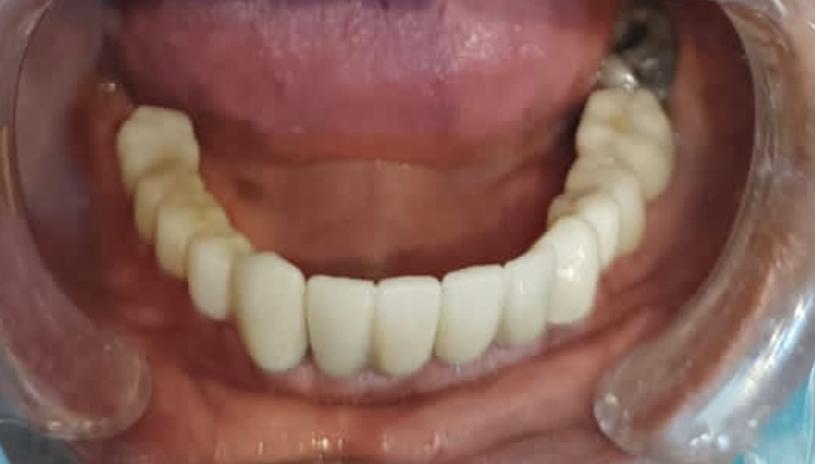

Post-operative clinical picture: Post-op, 6 months: Excellent bone height. Adequate Soft tissue healing